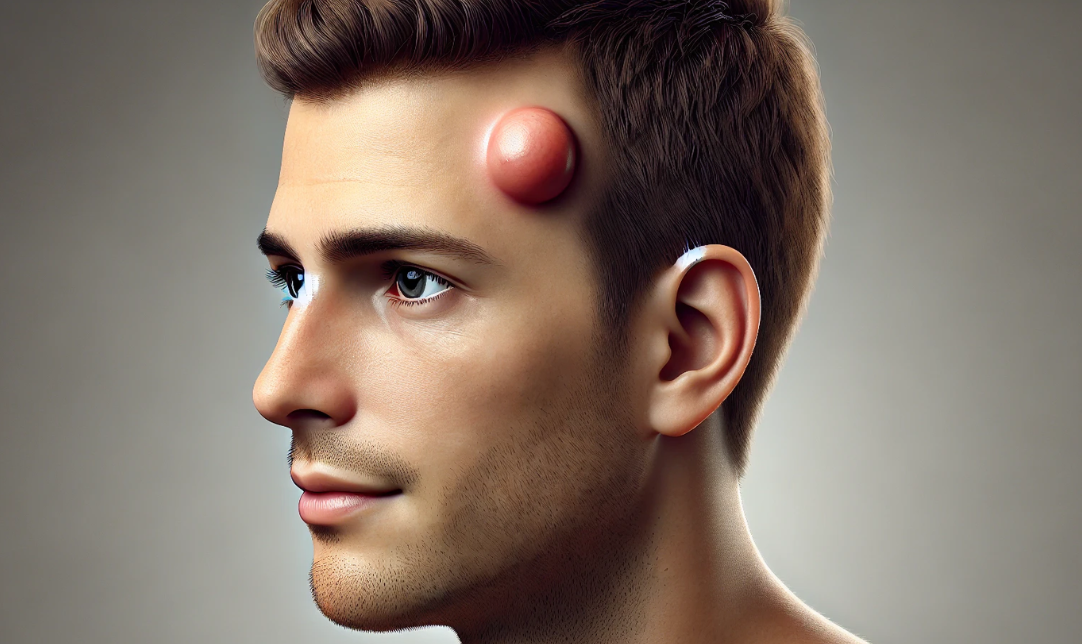

1. Lipoma

Lipoma adalah benjolan jinak yang terbentuk dari jaringan lemak di bawah kulit.

Ciri-ciri: Benjolan lunak, bisa digerakkan, dan biasanya tidak menimbulkan nyeri.

Lokasi umum: Leher, bahu, punggung, atau lengan.

Penanganan: Umumnya tidak berbahaya dan hanya diangkat jika mengganggu penampilan atau kenyamanan.